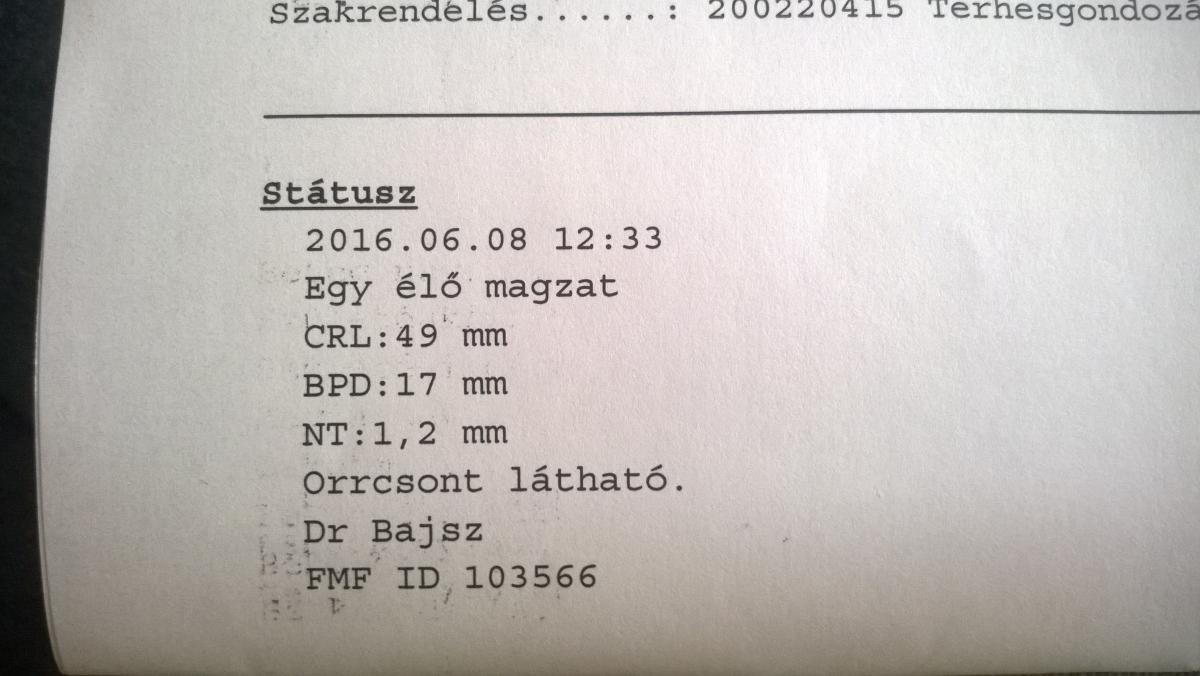

Megkaptam a genetikai UH leletét is, minden rendben van: